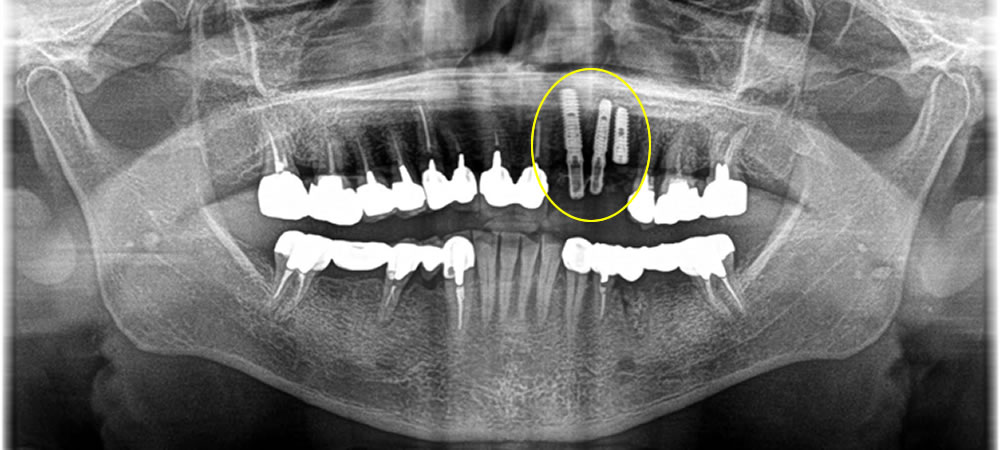

保存不可能な歯を抜歯後にインプラントで治療した症例

こちらは歯がグラグラして他院にて保存不可と診断された患者さまです。インプラント専門の当院にてインプラント治療を行いたいとの事でお越しいただきました。

前歯なので、審美的要素を重要視し歯茎が下がる事を極力抑えるために抜歯即時でインプラントを埋入し、骨を作る処置も同時に行いました。

抜いた時には唇側の骨が欠損してしまっていましたが、無事歯茎が下がる事を最小限に抑え上部の歯を作成する事ができました。